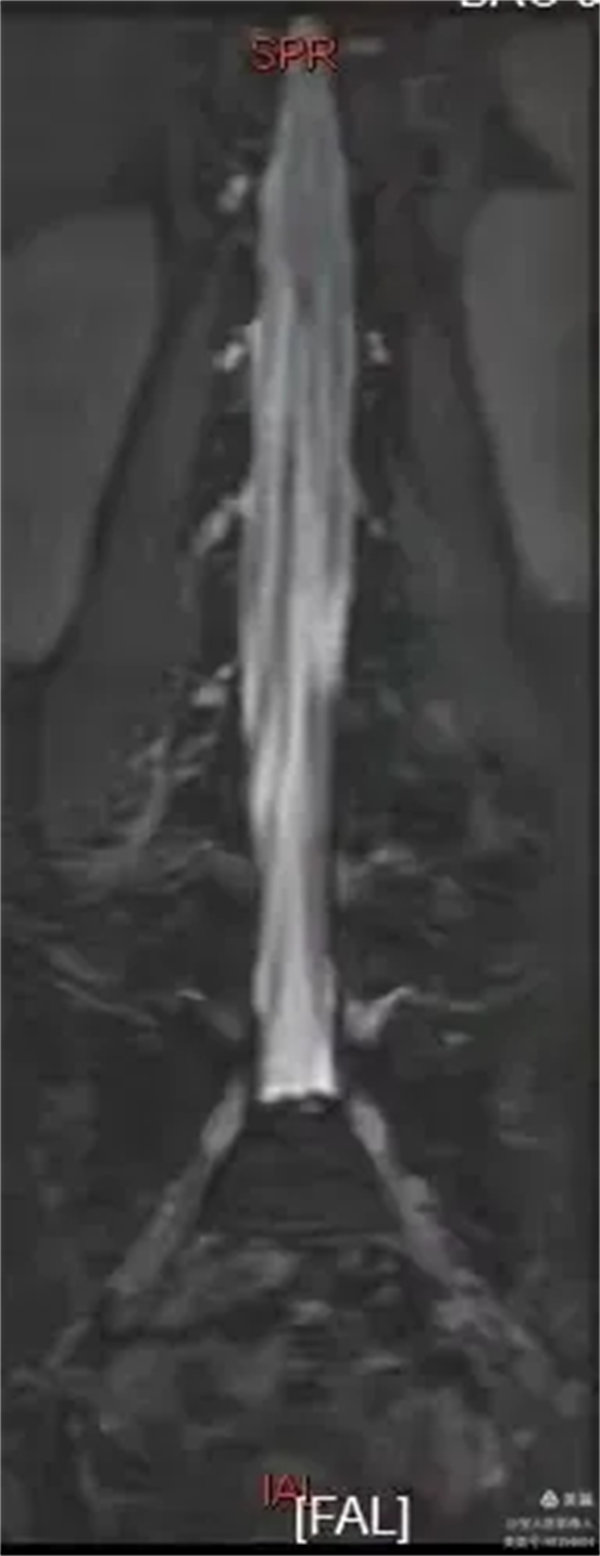

最大密度正面图,显示腰段硬膜囊内脑脊液(高信号),多条终丝(线状稍低信号)纵向走行清晰。

最大密度正面图,显示腰段硬膜囊内脑脊液(高信号),多条终丝、腰神经及骶神经(线状稍低信号)走行清晰。